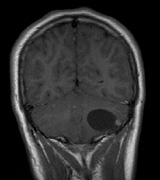

Neurologic Findings INTRACRANIAL LESIONS. Mental retardation and seizures in TSC are often associated with benign CNS astrocytic hamartomas.131 On imaging, the cerebral lesions show three patterns:132

SEIZURES. Typically observed first in infancy, seizures are a common presenting sign of TSC and a frequent source of morbidity. The seizures often begin as “salaam spasms”—repetitive myoclonic spasms that produce head nodding with associated extension/flexion of the trunk and limbs. They often progress to grand mal seizures25,116 and may be difficult to control. Vigabatrin has been advocated for control of infantile spasms but it carries a risk for irreversible visual field loss. Other treatments include corticosteroids, adrenocorticotrophic hormone, and a ketogenic diet.25,137–139 Selective surgical excision of an “epileptogenic tuber” may be an option for intractable epilepsy.140 MENTAL RETARDATION. Mental deficiency, part of Vogt's diagnostic triad (adenoma sebaceum, epilepsy, mental deficiency),3 affects about 50% of patients overall.25,141 TSC2 mutations may carry a higher risk than TSC1.142 AUTISM. This may affect 50% to 60% of TSC patients, possibly correlating with numbers of cerebellar and temporal tubers.25,143,144 Visceral Findings Patients with TSC may have renal, cardiac, pulmonary and other visceral involvement. RENAL. The TSC2 gene was localized by linkage with the polycystic kidney disease gene in patients with TSC and polycystic kidneys. This represents a contiguous gene syndrome in which adjacent genes (PKD1 and TSC2) are deleted together.145–147 Multiple angiomyolipomas of the kidney are benign hamartomas of blood vessels, smooth muscle, and fat. By 10 years of age, the frequency of angiolmyolipomas is 75%, similar to adults.148 The fat signal of angiomyolipomas helps to distinguish them from renal cell carcinoma.25 Renal insufficiency/failure may be the complication of both cystic disease and angiomyolipomas and is one of the leading causes of morbidity and mortality in TSC.138,149 CARDIAC. Rhabdomyoma are usually multiple, typically asymptomatic, and often regress with age.150,151 PULMONARY. Lymphangioleiomyomatosis is a progressive lung disease characterized by bronchiolar smooth muscle infiltration and cystic changes of the lung parenchyma. About 1% of adult females with TSC are affected.116,152,153 OPHTHALMIC FEATURES The principal ophthalmic manifestations of TSC are in the posterior segment. Astrocytic Retinal Hamartomas Although in Van der Hoeve's original description the term phakoma or phakomata was a generic term for the tumors occurring in various organ systems,1 it has become associated with the retinal astrocytic tumors of TSC,3 which occur in about 50% of affected patients and are bilateral in 25% to 30% (Table 3, Fig. 16).154,156